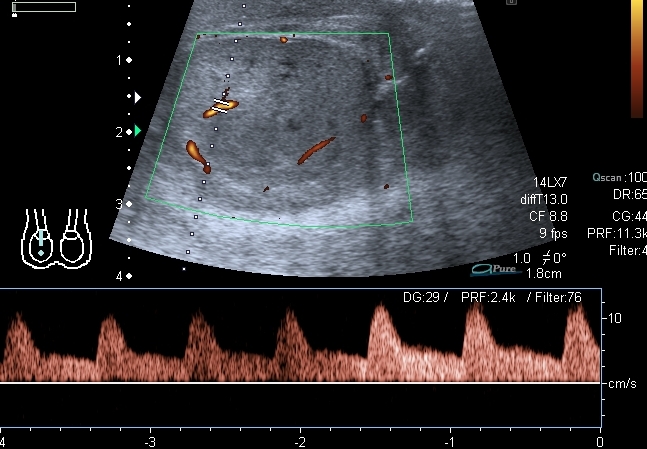

Пациент выписался домой, пока на контроль не появлялся. Через три дня после операции кровоток в яичке был достаточно "живой", нерестриктивный (см. скан с триплексом), но большое сомнение оставил приличный по размерам гипоэхогенный участок. Да и анамнез - около двух дней без кровотока... Во время операции хирурги делали пробу - надсекали оболочку яичка - получили капилярное кровотечение, на основании чего заключили, что яичко жизнеспособно. Я про такую методу , честно говоря, не слышал, дай Бог, чтоб эта проба работала.Dr Alex писал(а):Интересно, "ожило" ли яичко?